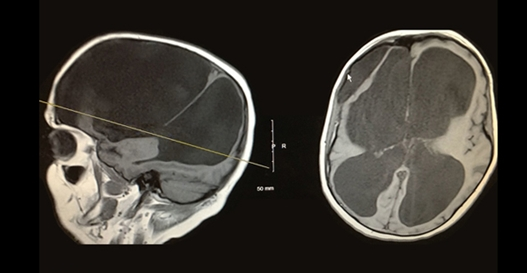

“宝宝头大,一看就很聪明!”出生三个月的豆豆因为头比较大,一直被爷爷奶奶夸是个聪明宝宝。但是豆豆的母亲发现宝宝的头围过大,已经和正常宝宝有些不一样,头围超出正常范围,而且经常伴有哭闹、呕吐、抽搐、斜视等现象。咨询一些熟悉的宝妈们,得到了一个惊人的回答:“应考虑宝宝是否患有脑积水?”豆豆母亲慌忙带着豆豆到了医院检查一番,结果真的是脑积水。脑积水是什么,脑积水症状究竟有哪些?下面将详细解答。

在婴儿期,脑积水较明显的迹象通常是头围迅速增加或头部异常增大。其他症状可能包括呕吐、嗜睡、易怒、眼睛向下偏斜,以及癫痫发作。

脑积水是如何诊断的?

脑积水是通过临床神经病学评估和使用头颅成像技术来诊断的,例如超声波检查法计算机断层摄影,磁共振成像或者压力监测技术。医生根据个人的年龄、临床表现以及已知或怀疑的大脑或脊髓异常的存在来选择合适的诊断工具。